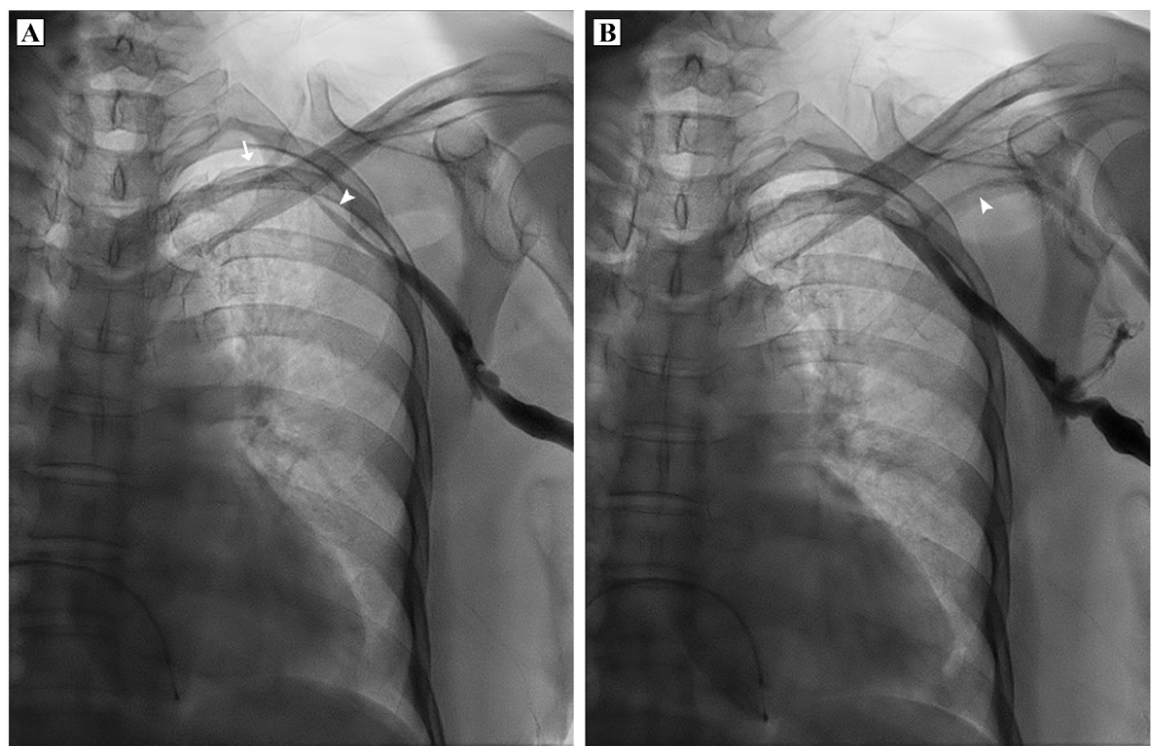

A woman in her 60s presented with symptomatic complete heart block and was advised permanent pacemaker implantation. During the procedure, left axillary vein access was attempted using fluoroscopic landmarks but was not successful. A venogram was taken subsequently, which showed severe spasm of the axillary vein (Figure 1A and Video 1). Normal saline was infused from the ipsilateral peripheral venous access but venous spasm persisted. Intravenous nitroglycerin was administered from the ipsilateral access. A repeat venogram performed after 10 minutes showed resolution of the spasm (Figure 1B and Video 2). Successful venous puncture could be performed using the venogram as reference.

The axillary vein is the preferred puncture site for insertion of transvenous leads during cardiac implantable electronic device implantation. Axillary vein spasm is an important cause of failed venous cannulation and should be suspected when access cannot be obtained despite multiple attempts. It can be diagnosed by performing a venogram from ipsilateral peripheral cannula. The features include marked reduction in lumen and contrast opacification of the axillary vein. The cephalic vein may or may not be visualized during the spasm. The etiopathogenesis is not well understood. Implicated factors include chemical irritation caused by intravenous contrast, administered during initial venogram prior to puncture, and vessel trauma by repeated puncture attempts.